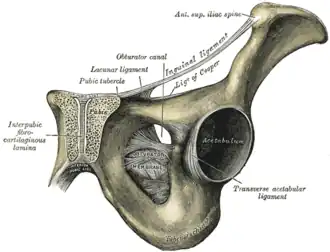

Right hip bone. External surface.

Right hip bone. External surface. -